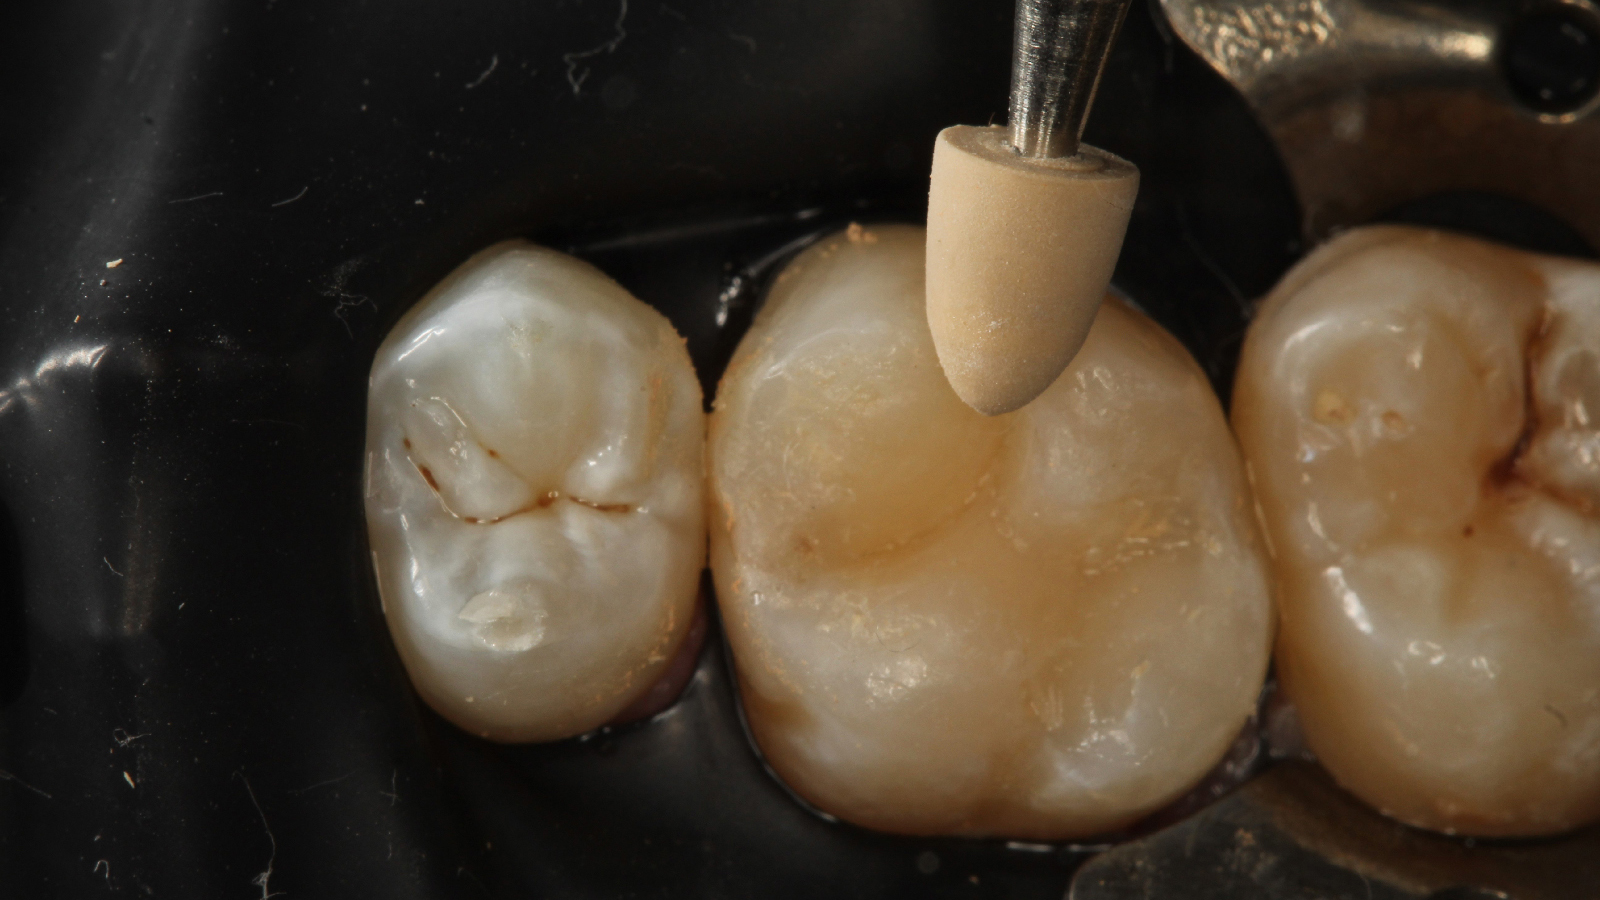

Every day, dentists manage challenging cases with the help of Charisma Diamond & Topaz ONE Shades. Check out what your colleagues say about the product and see the broad variety of cases already done by them!

ONE shade cases – great results around the world

Before & After Cases

Life Hacks for successful posterior restorations